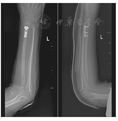

(3)切开复位组:闭合复位尺骨骨折,自尺骨近端打入1枚已预弯弹性髓内针(瑞士Synthes公司生产,直径2.0 mm或2.5 mm)经髓腔穿过骨折线至骨折远端。桡骨骨折采用背侧入路切口,将桡侧腕伸肌肌腱牵向桡侧,拇长伸肌肌腱牵向尺侧。直视下牵拉复位骨折断端,纠正成角、旋转畸形。予4孔或5孔T型接骨板(美国施乐辉公司)固定桡骨远端(图3)。